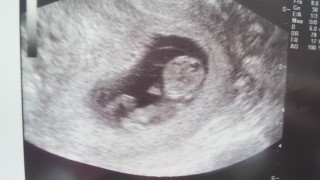

この間、検診行った時の写真です。

先生が、すごく大きくなったねー!

順調だよって言ってくれて安心しました!

元気に手を動かしてるのも確認できて嬉しかったです。